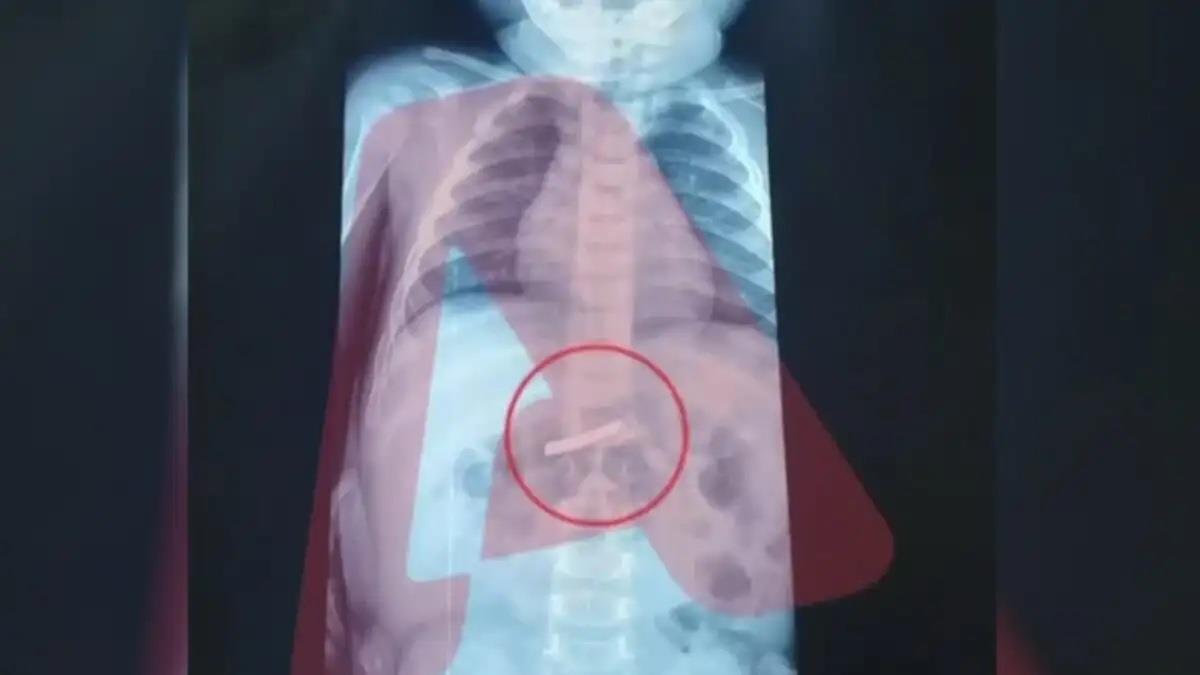

Σύμφωνα με τις πρώτες πληροφορίες, το παιδάκι μεταφέρθηκε άμεσα για χειρουργική αντιμετώπιση, καθώς η κατάσταση κρίθηκε επείγουσα. Πριν από την επέμβαση, οι γιατροί προχώρησαν στις απαραίτητες εξετάσεις και συγκεκριμένα σε ακτινογραφία, η οποία επιβεβαίωσε τις ανησυχίες των γονιών: στο στομάχι του παιδιού υπήρχε πράγματι ένα ξυραφάκι, όπως εκείνοι είχαν ήδη ενημερώσει το ιατρικό προσωπικό.

Η ακριβής θέση του αντικειμένου εντοπίστηκε με σαφήνεια, γεγονός που επέτρεψε στους χειρουργούς να σχεδιάσουν με προσοχή την επέμβαση. Με γνώμονα την ασφάλεια του παιδιού και τη μέγιστη δυνατή ακρίβεια, προχώρησαν στην αφαίρεση του ξυραφιού, αποφεύγοντας επιπλοκές.